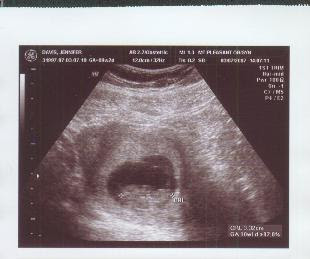

Here are our ultrasound photos from today:

This one is the cool one. Look at the bottom. That squiggly line is the heart beat of our baby: